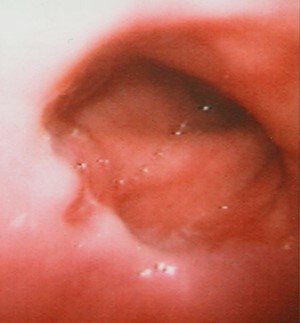

Pulsiyon divertikuldur. QB-nun boyun hissəsinin arxa divarında, selikli qişa və selikaltı əsasın əzələlər arasından kənara qabarması nəitcəsində əmələ gəlir. Üst ezofagus və ya farinqoezofageal divertikul da adlandırılır.

Yuxarı sfinkterin dismotorikası və ya diskoordinasiyası mənfəzdaxili basincın təzyiqin artmasına, sonuncu isə QB-nun arxa divarının zəif əzələ lifləri arasından selikli qişa və selikaltı qatın kənara qabarmasına səbəb olur (krikofaringeal əzələ ilə udlağın aşağı büzücü əzələləri arasındakı zəif hissə Cillian (Killian) üçbucağı adanır).

Diaqnostikası

Dəqiqləşdirmə

Diaqnozun dəiqiləşdirilməsi üçün kontrastlı Rentgenoloji müayinələr, KT və çox ehtiyatla endoskopiya edilir.

- Kontrastlı Rh-qrafiya - diaqnozu dəqiqləşdirən müayinədir.

- Endoskopiya - divertikulun perforasiyası təhlükəsinə görə çox ehtiyatla aparılmalıdır.